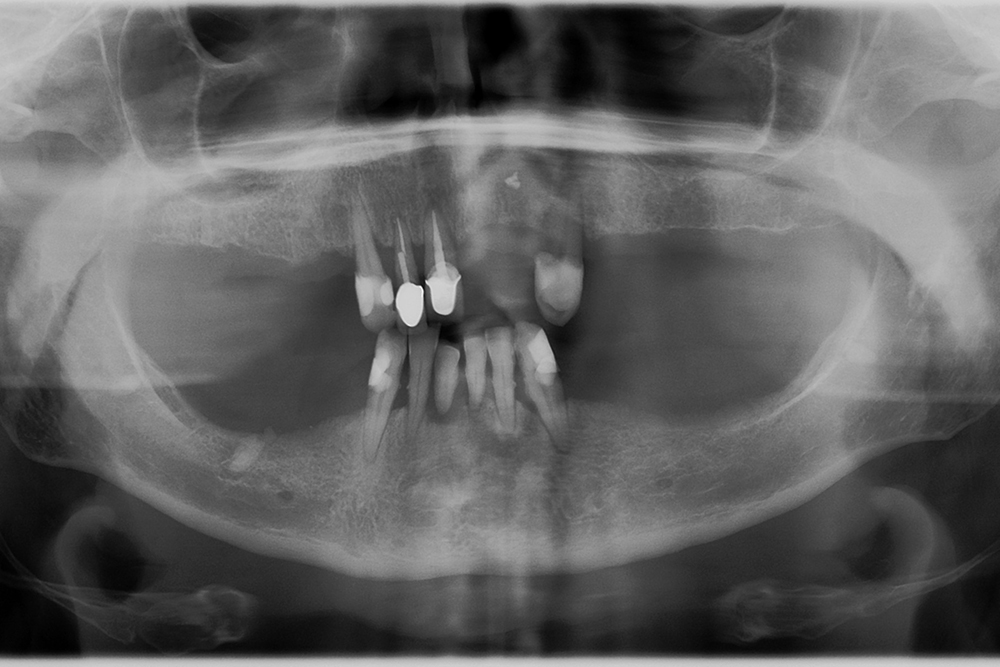

Ripristino dell’arcata superiore ed inferiore su overdenture su barra